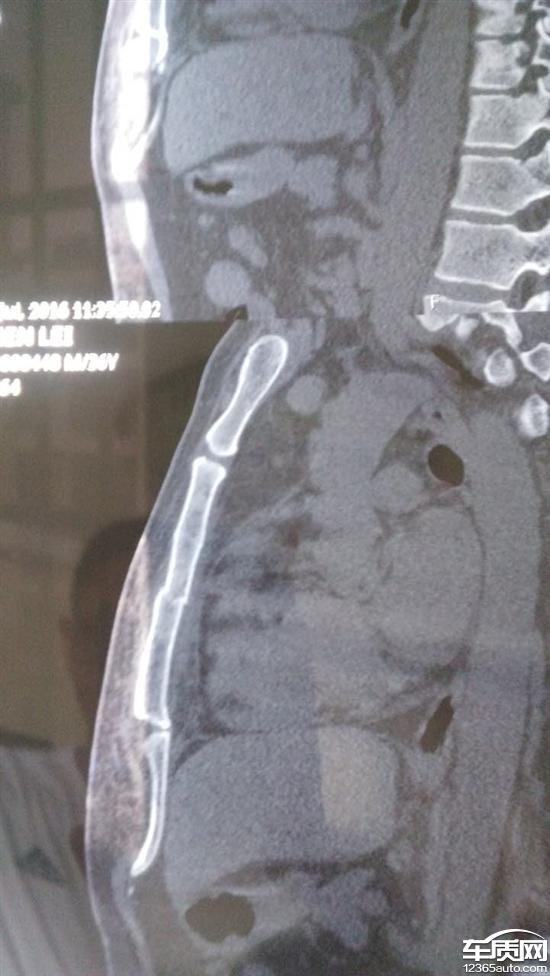

晚不到7点,驾驶车在省道行驶,全车里程在3百多点,当时行驶速度在六十到七十之间,车内开空调,前四十公里一路安好,在一次等红灯后,感觉车子提速有发肉现象,心想开空调新车动力有下降实属正常,,前面路上出现行人,减速,突然没有刹车,再刹,方向突然左偏离,无刹车,眼睁着看车直接上护栏,气囊炸开,驾驶人身系安全带但是安全带无拉力,直接前冲顶上方向盘,造成驾者胸骨当场骨折,后座人员健安。车子送4S店维修拆解,本人目测除左前刹车抱死,余下车轮正常,左前轮摩擦后高温至刹车罩壳都起皮,事后简单跟维修经理沟通刹车及安全带问题,要求上报厂家,事后因个人家庭等原因,没有再沟通,现要求厂家调查车辆原因,给本人一交代!车子安全问题严重,特别是刹车及安全带。